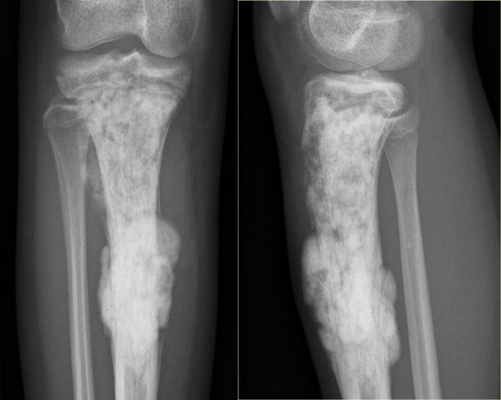

X線、CT、病例檢查

骨癌圖片

骨癌